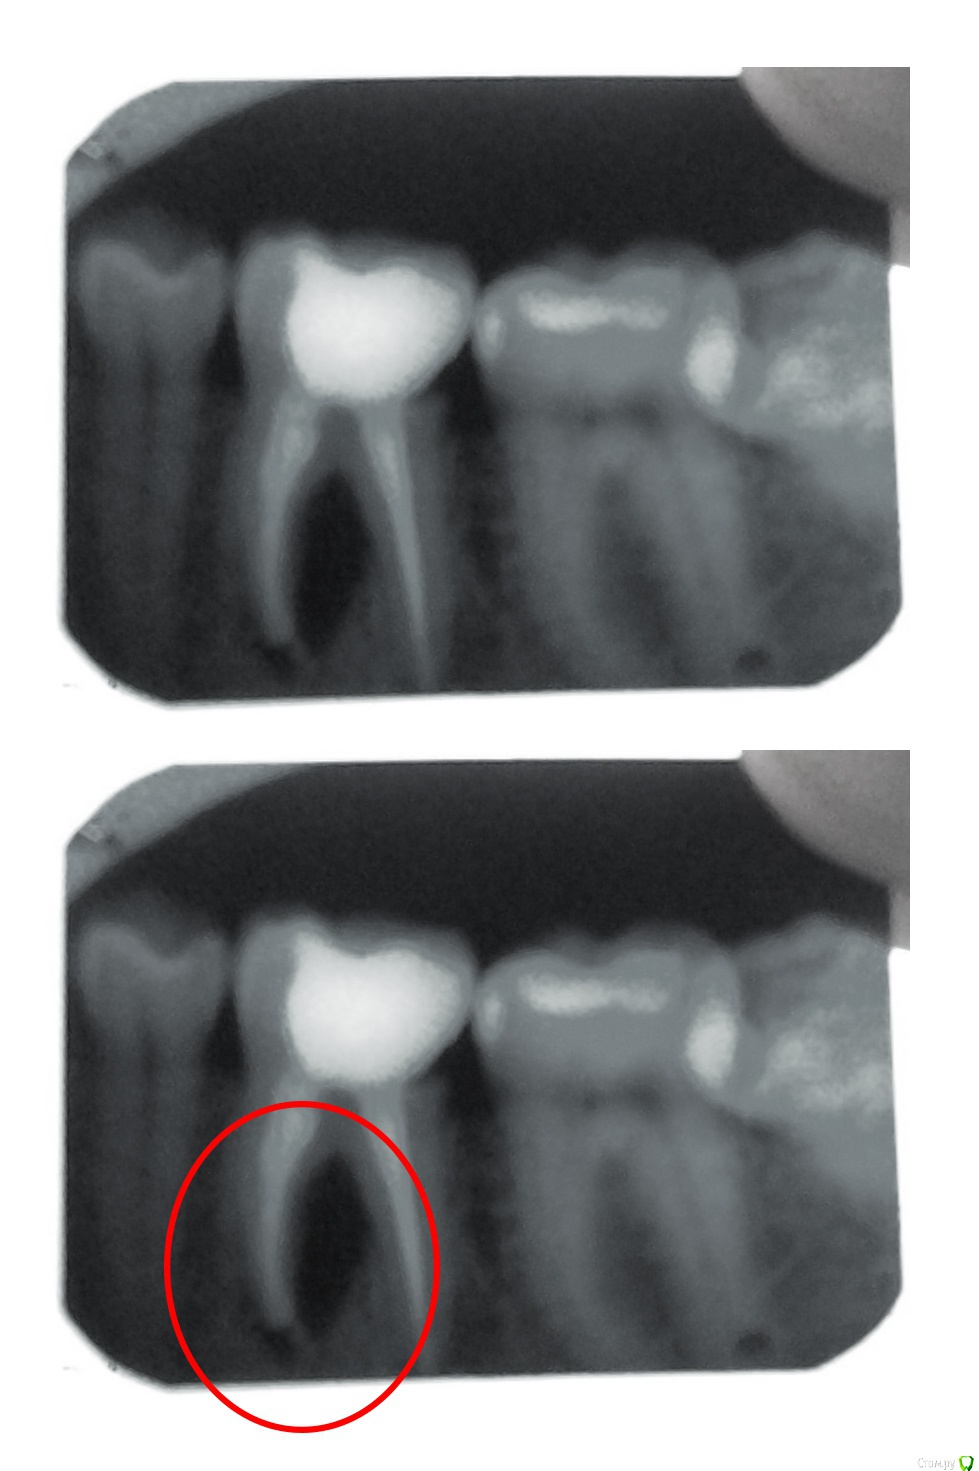

Alex1990 Опубликовано 7 мая, 2017 Поделиться Опубликовано 7 мая, 2017 Здравствуйте мне 26 лет. 8 лет назад мне пролечили зуб (46-й если не ошибаюсь), удалили нерв и запломбировали. Около 2-х месяцев назад на десне под зубом появился жёлтый пузырёк, потом пропал, через неделю опять появился, потом снова пропал, при этом ни зуб, ни десна не болели и не болят. Через некоторое время ранка на десне стала постоянным явлением периодически из неё сочился гной. Я обратился к стоматологу, мне сделали рентген и определили, что у меня уже длительное время присутствует воспаление между корнями этого зуба и как результат этого воспаления на десне образовался свищевой ход. Также врач сказала, что каналы зуба были пролечены хорошо. Мне посоветовали удалить зуб. Подскажите, можно ли спасти зуб, ведь он совершенно не болит, не болит и десна? Ссылка на комментарий

inSight Опубликовано 7 мая, 2017 Поделиться Опубликовано 7 мая, 2017 клкт, перелечивание, обязательно коронка. Реинфецирование вследствие потери герметизма пломбы. 1 Ссылка на комментарий

St. Опубликовано 7 мая, 2017 Поделиться Опубликовано 7 мая, 2017 Подскажите, можно ли спасти зуб, ведь он совершенно не болит, не болит и десна? Не болит потому что есть свищ, это увы не показатель здоровья.Вариантов с зубом 3:1. пробовать перелечить2. удалить и имплант3. ничего не делать ( самый непрогнозируемый вариант, потому что в любой момент может начато болеть или припухнуть). Если есть желание и найдете доктора можно пробовать перелечить каналы. Процедура сложная и без гарантии, но если все получится, то удастся сохранить родной зубЕсли хотите гарантий - удаление и имплант. Ссылка на комментарий